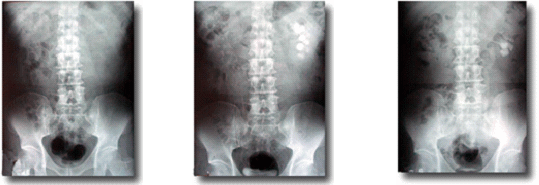

経静脈的腎盂造影